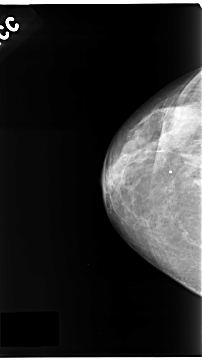

C_0123_1.LEFT_CC

RIGHT_CC LINES 4696 PIXELS_PER_LINE 2616 BITS_PER_PIXEL 12 RESOLUTION 50 NON_OVERLAY